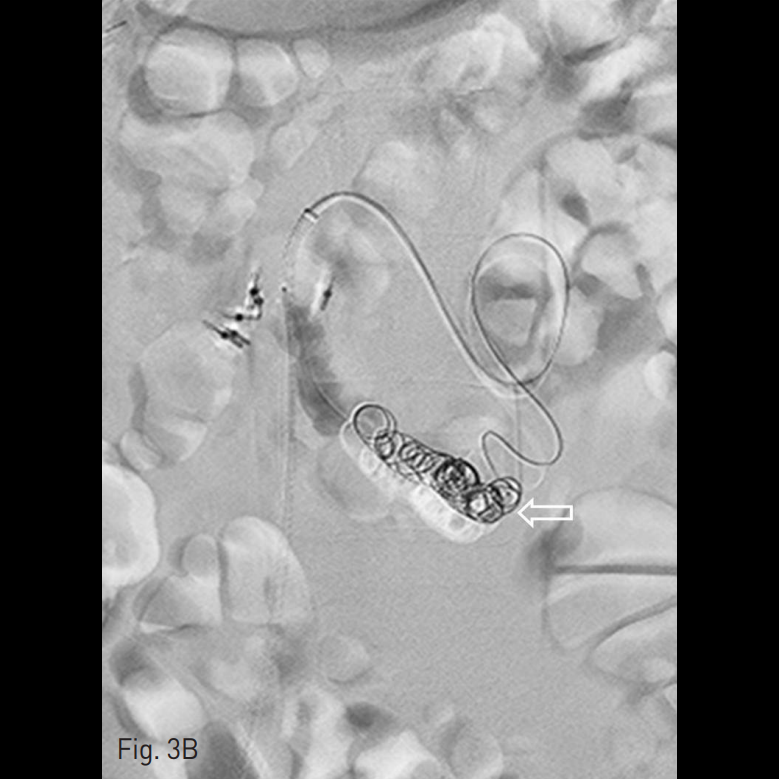

마지막 내시경적 치료 이후에 검사한 전산화 단층촬영 (CT, Computed Tomography)에서 십이지장 제3부와 제4부에 걸쳐 hemoclipping된 십이지장 정맥류가 있음 (Fig. 2A-C). 십이지장 정맥류는 상장간막정맥에서 기시하여 좌측 부신장정맥으로 연결되는 장간막신장정맥단락(mesenterorenal shunt)에 위치했음.

Fig. 2

B-C. Duodenal varix (arrowhead) is connected with tortuous and dilated mesenterorenal shunt (open arrow). The mesenterorenal shunt starts from superior mesenteric vein and drains to left accessory renal vein (not seen on this image).